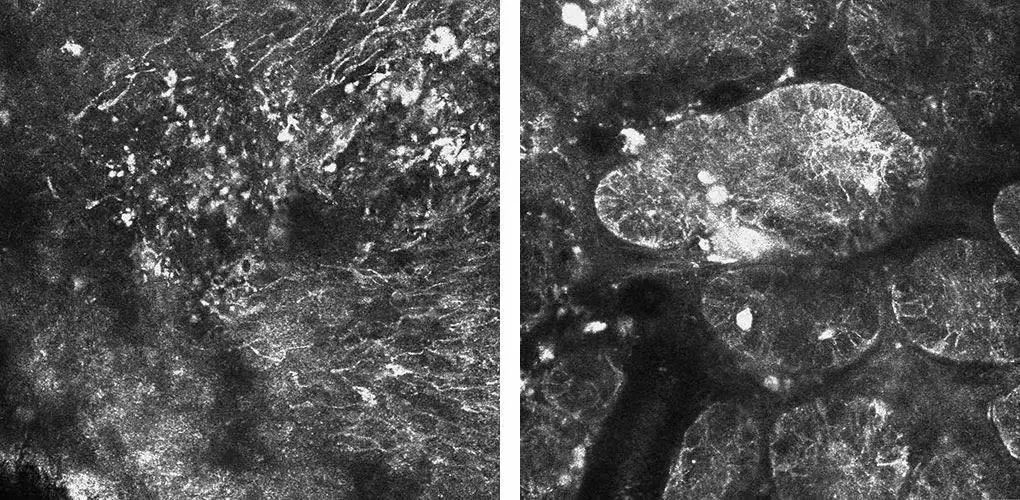

“这种技术就像给皮肤做CT扫描,不需要切开皮肤就能看到细胞层面的变化。”黄拯球解释道,它能够实时、高清地显示表皮及真皮浅层的微观结构,对恶性肿瘤的早期诊断特别有价值。

刘女士接受了检查,检查结果所显示的典型影像学特征让医生高度怀疑为基底细胞癌。